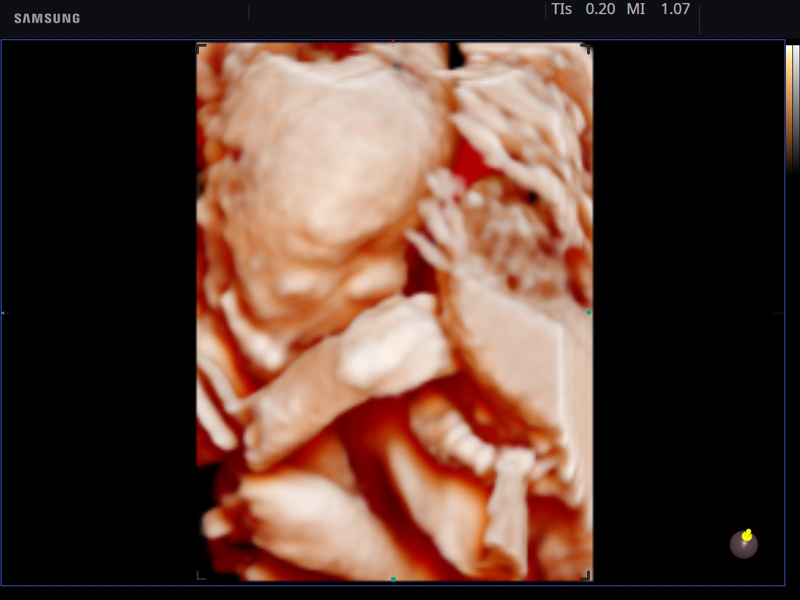

- Модуль Realistic Vue - программа реконструкции реалистичного 3D УЗИ, при котором на объемное изображение накладывается виртуальный источник освещения. Специальный процессинговый алгоритм воспроизводит трехмерную анатомию плода с исключительной детализацией.

Примеры клинических изображений УЗИ аппарата hs40 A-RUS (Samsung Medison)